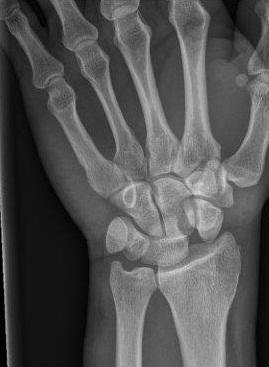

Ian Bickle, Radiopaedia.org. From the case rID: 46695

Fracture du scaphoïde

Entorse scapho-lunaire (distance scaphoïde-lunatum > 2mm)